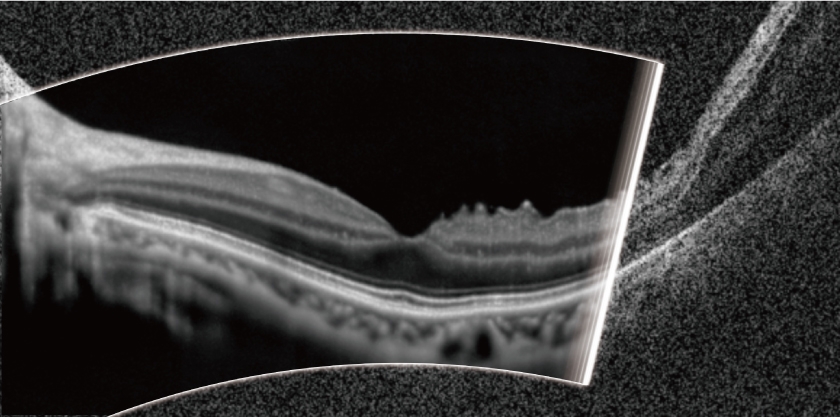

ワイドエリアスキャン